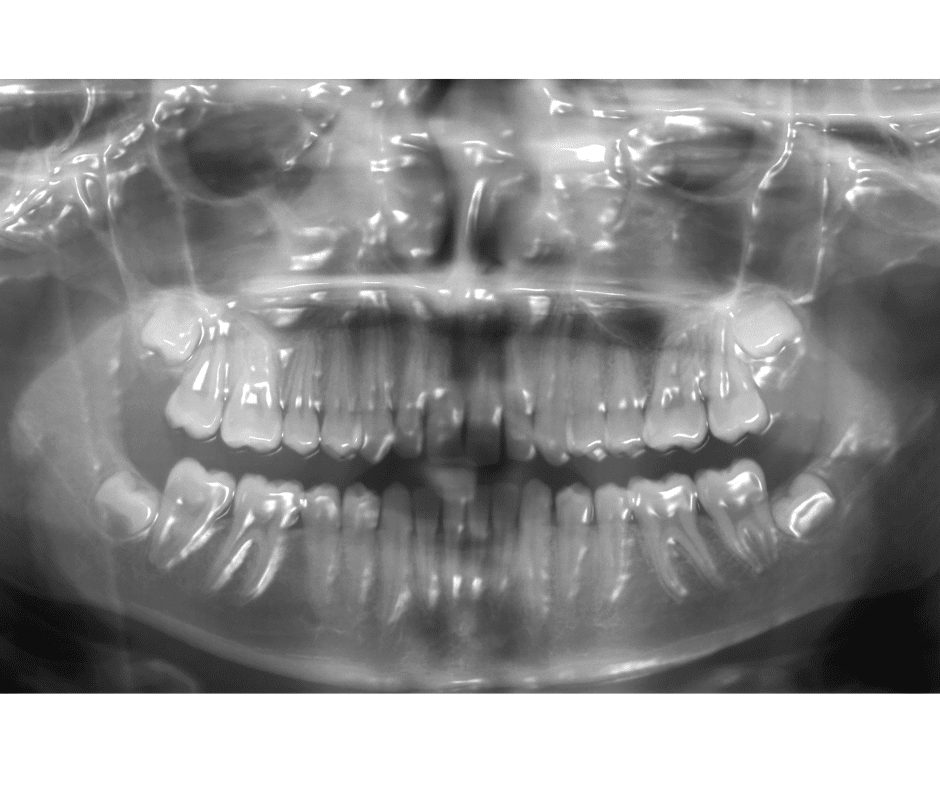

3d x-rays

Digital X-Rays

Less Radiation, better images.

Low Radiation Digital X-rays use 90% less radiation and provides immediate images to quickly diagnose hidden problems. We are not only able to reduce your exposure to radiation but also increase the diagnostic proficiency. In addition to increased diagnostics, we reduce the amount of harmful chemicals and other waste materials associated with traditional X-ray technology.